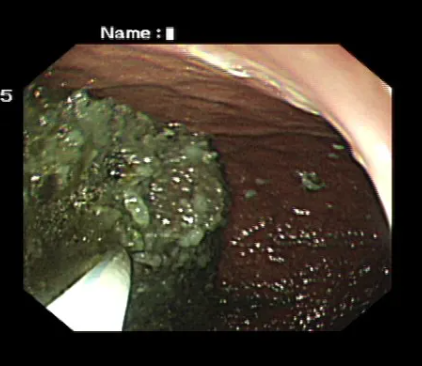

內(nèi)鏡下治療

通過胃鏡伸入器械,如圈套器、網(wǎng)籃、碎石器等,將結(jié)石“切碎”、“鉗碎”或“套取”出來,被分解成小塊的結(jié)石會(huì)隨著消化道自然排出,或者用藥物進(jìn)一步溶解后排出。創(chuàng)傷小,恢復(fù)快。

■ 機(jī)械碎石法:用圈套器、異物網(wǎng)籃等器械將結(jié)石切碎或分解。